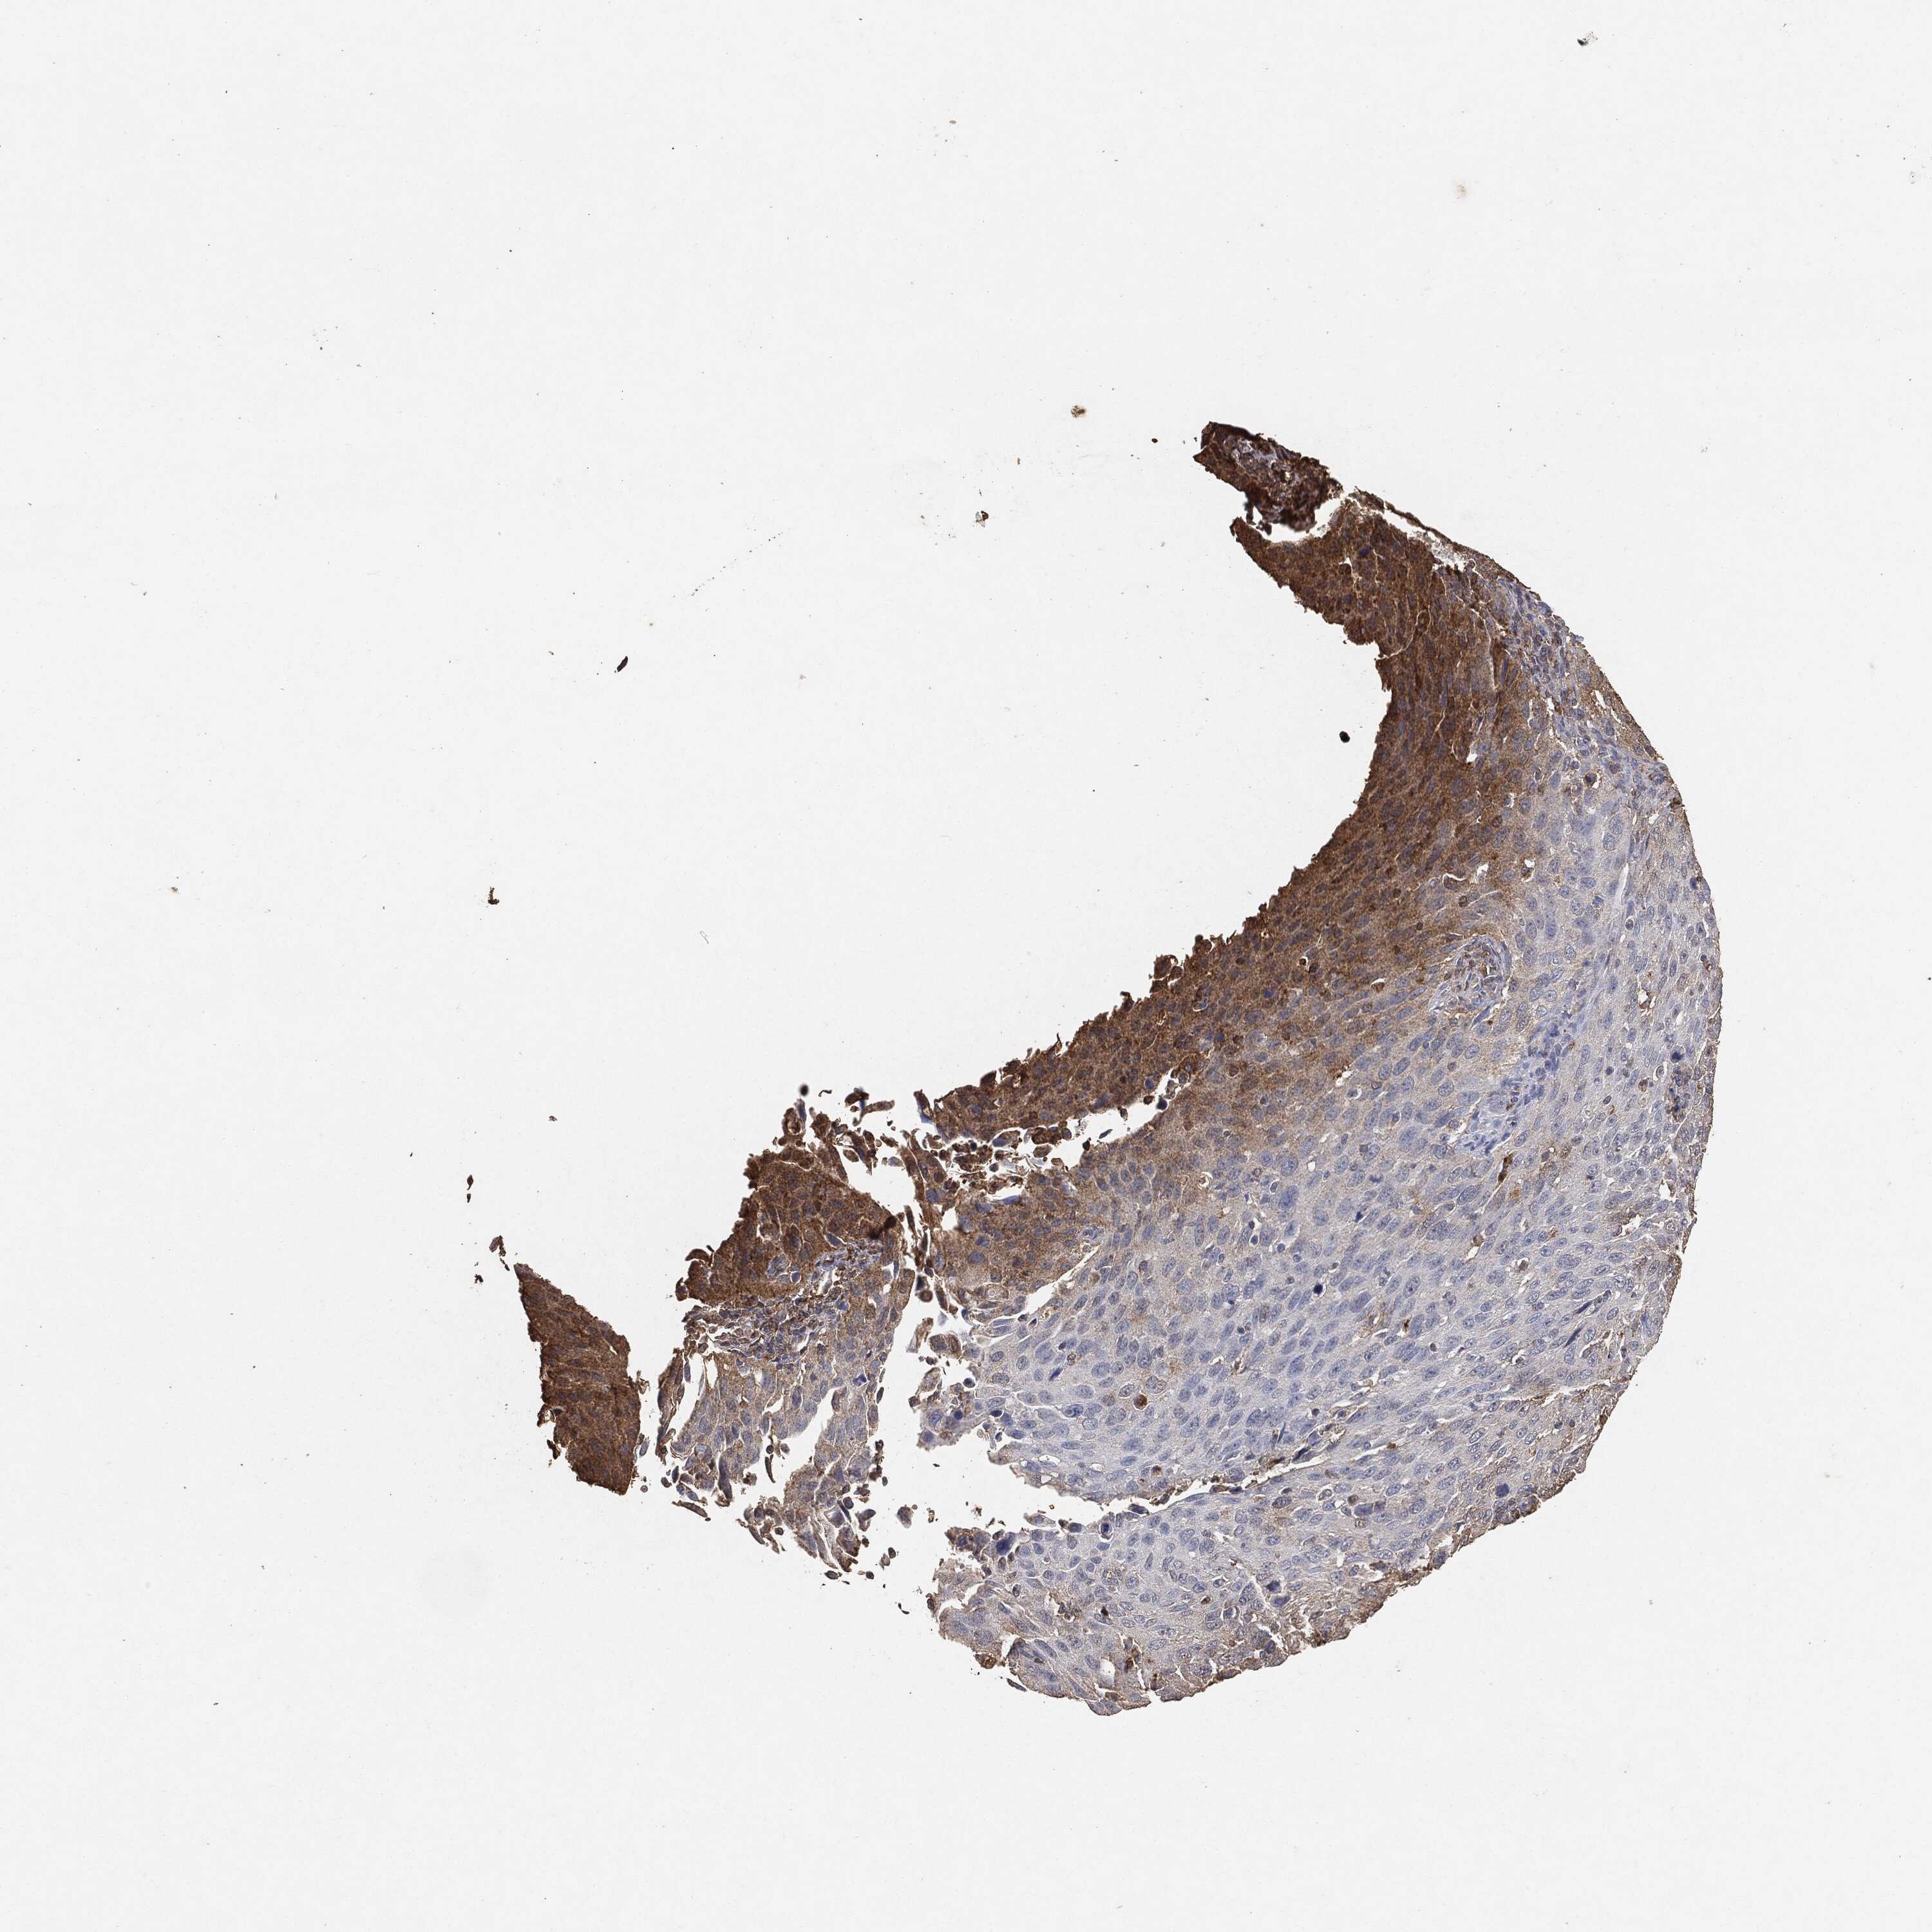

CERVICAL CANCER - Protein expressioni

A mouse-over function shows sample information and annotation data. Click on an image to view it in a full screen mode. Samples can be filtered based on level of antibody staining by selecting one or several of the following categories: high, medium, low and not detected. The assay and annotation is described here.

Note that samples used for immunohistochemistry by the Human Protein Atlas do not correspond to samples in the TCGA dataset.

Antibody stainingi

Antibody staining in the annotated cell types in the current human tissue is reported as not detected, low, medium, or high, based on conventional immunohistochemistry profiling in selected tissues. This score is based on the combination of the staining intensity and fraction of stained cells.

Each image is clickable and will lead to virtual microscopy that enables deeper exploration of all samples and also displays staining intensity scores, fraction scores and subcellular localization as well as patient and tissue information for each sample.

Adenocarcinoma, NOS

Squamous cell carcinoma, NOS